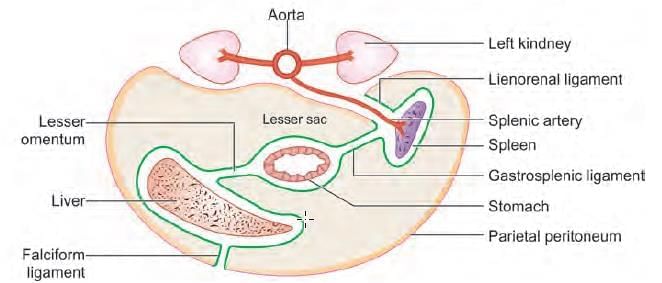

A 25-year-old male presents to emergency with left upper quadrant pain, upon examination spleen was measured to 20 cm and further extending to the mid umbilicus. The extension of the spleen to left lower quadrant was prevented by: (NEET-PG 2021)